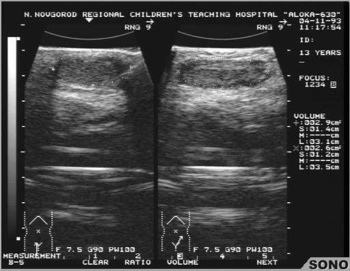

• Сонография области мошонки

Ультразвуковое исследование дает большое количество информации и форме, размерах, структуре, а также кровоснабжении семенников и является важным диагностическим инструментом.

Диагностика

Для диагностики данного заболевания необходимо обратится к андрологу или эндокринологу. Проводится пальпация мошонки, визуальный осмотр, измеряются длинник, поперечник и объём яичек. Проводится ультразвуковое исследование мошонки. Проводится спермограмма пациентам старше 18 лет, оценивается качество спермы, её объём, реологические свойства. Оцениваются сперматозоиды, их количество, форма, скорость движения. Проводится забор крови для определения уровня тестостерона и активной фракции тестостерона. При подозрении на наследственное хромосомное или генетическое заболевание проводится обследование у врача-генетика, проводится кариотипирование, хромосомный анализ и исследование генов.